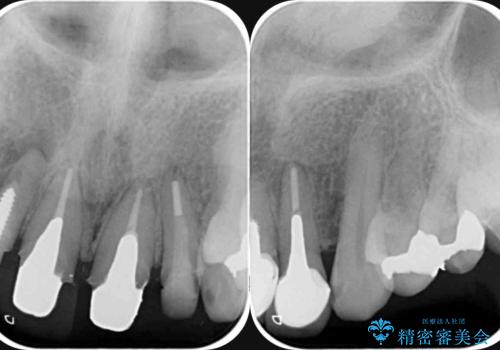

- 以前治療した前歯のセラミックの歯ぐきの位置がかわってしまい境目の変色の改善を希望して来院されました。

大きな穿孔が見られた、右上側切歯の抜去をこないブリッジの設計を含めた前歯の審美性の改善を目的とするセラミック治療を行いました。